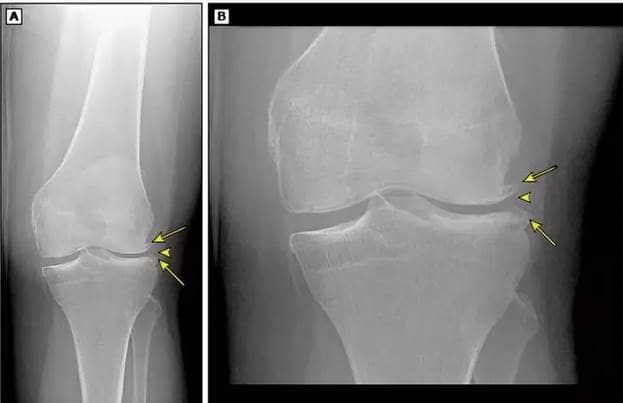

Krew usuwa sole ze stawów. Jeśli słabo krąży, sole się nagromadzą. Są to sole wapniowe i sodowe, które znajdują się w prawie wszystkich produktach i które są niezbędne dla człowieka. Jednak gdy odkładają się w stawach, prowadzą do powstania twardych narośli kostnych (osteofitów) na powierzchni stawu. Z czasem mogą się powiększać i ściskać zakończenia nerwowe. Prowadzi to do silnego bólu. Zwykle ludzie nie mogą znieść tego bólu i zwracają się do profesjonalistów. Ale jeśli ból jest bardzo silny, tylko operacja może pomóc. Jeśli ból jest rzadki i nie jest silny, można go rozwiązać za pomocą metod terapeutycznych, ale należy się spieszyć.

Narośle kostne w stawie kolanowym